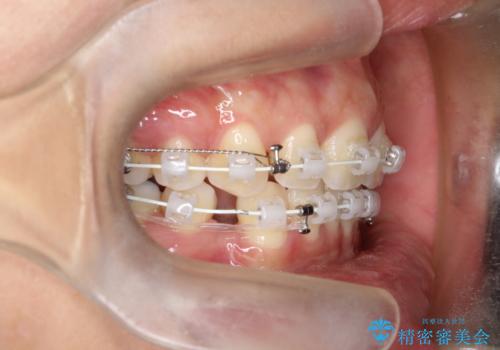

2. 【審美ワイヤー】口元を下げたいの治療中